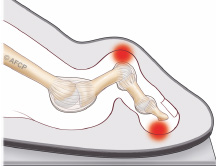

Les subtilités de la technique chirurgicale varient selon les chirurgiens. Néanmoins, tous réalisent une libération latérale des tissus mous et une coupe osseuse (ostéotomie du métatarsien type scarf dans notre institution). Une ostéotomie de la première phalange (type Akin) est parfois nécessaire selon la déformation de celle-ci. Ces gestes permettent de restaurer un valgus physiologique de l’articulation métatarso-phalangienne et de rechausser les sésamoïdes sous le premier métatarsien (figure ci-dessous). Notons qu’en cas d’irréductibilité de la déformation (testée en consultation) ou d’arthrose importante (vue sur le bilan RX), une arthrodèse (fusion) de l’articulation, en position réduite, sera réalisée.